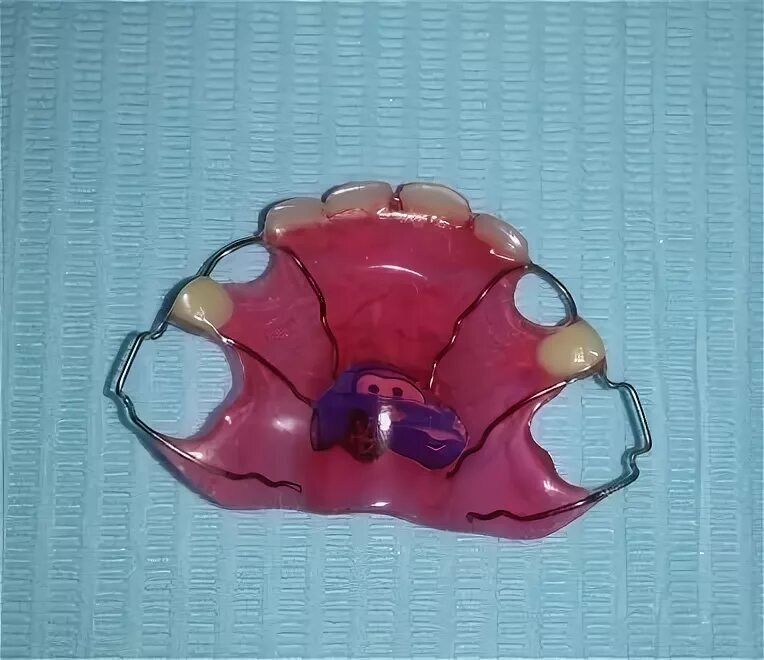

Съемные профилактические протезы: примеры и фотографии